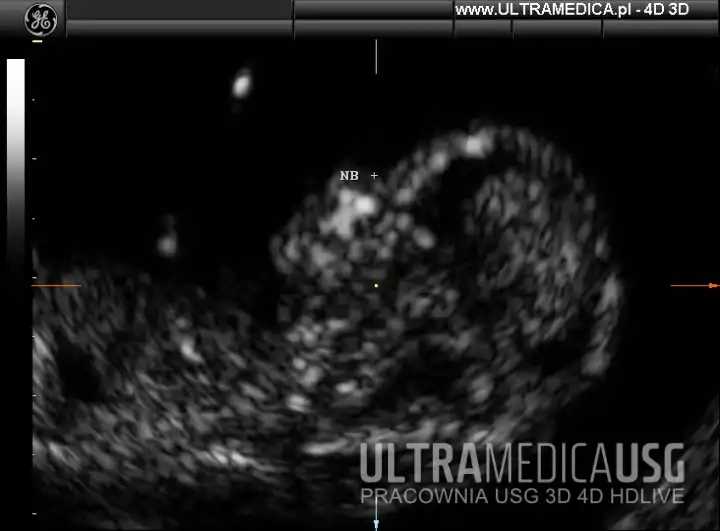

Lista tych markerów jest cały czas rozwijana i uszczegółowiana na podstawie toczących się na całym świecie badań nad chorobami genetycznymi, np. dla zespołu Downa markerami dla pierwszego trymestru są między innymi pomiar przezierności karku (NT), ocena fali tętna w przewodzie żylnym (DV), kość nosowa (NB), budowa kości szczękowej oraz ocena zastawki trójdzielnej (TV).

- ocena obecności kości nosowych - marker zespołu Downa,

Film: USG ciąży 1 trymestr - kości nosowe płodu - USG 3D